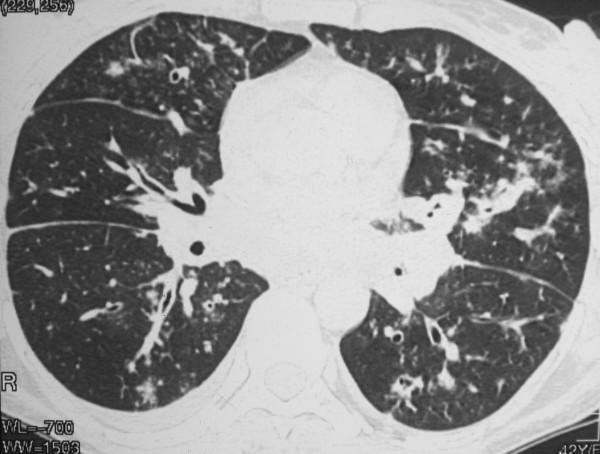

Approximately 90% to 95% of Kaposi sarcoma cases occur in human immunodeficiency virus - infected homosexual and bisexual men. Pulmonary Kaposi sarcoma is uncommon in women, and rarely considered as a potential cause of diffuse lung disease in women with acquired immunodeficiency syndrome. The disease is usually mistaken clinically for pulmonary infection. A 32-year-old woman was admitted with a 2-month history of dyspnea, evening fever, hemoptysis, weight loss, and generalized adenomegaly. Physical examination showed erythematous macules in the lower limbs. Skin and open lung biopsy demonstrated Kaposi sarcoma. Computerized tomography demonstrated peribronchovascular interstitial thickening. Although uncommon, pulmonary Kaposi sarcoma should be considered in the differential diagnosis of diffuse lung disease in women with AIDS.

约90%至95%的卡波西肉瘤病例发生于感染人类免疫缺陷病毒的同性恋和双性恋男性。肺卡波西肉瘤在女性中并不常见,在获得性免疫缺陷综合征女性患者中很少被视为弥漫性肺病的潜在病因。临床上该病通常被误诊为肺部感染。一名32岁女性因2个月的呼吸困难、午后发热、咯血、体重减轻及全身淋巴结肿大入院。体格检查发现下肢有红斑。皮肤及开放性肺活检显示为卡波西肉瘤。计算机断层扫描显示支气管血管周围间质增厚。尽管罕见,但在艾滋病女性患者弥漫性肺病的鉴别诊断中应考虑肺卡波西肉瘤。